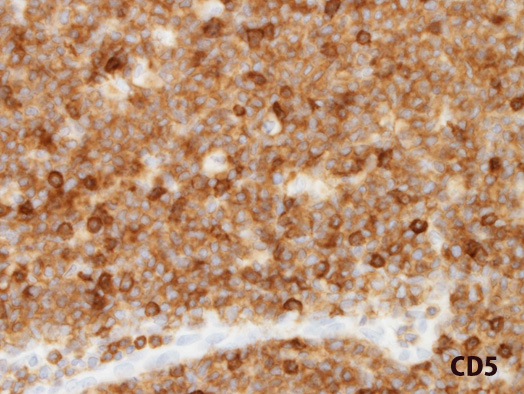

CD5a.jpg

CD5cyclin D1

CD5; 標本がやや厚切り切片。当院の染色ではMCL細胞は乏しい細胞質に染まる。教科書のようにきれいに細胞膜には染まらなかった。賦活の前処置のためかもしれない。混在するCD5+T細胞がより強く染まっている。